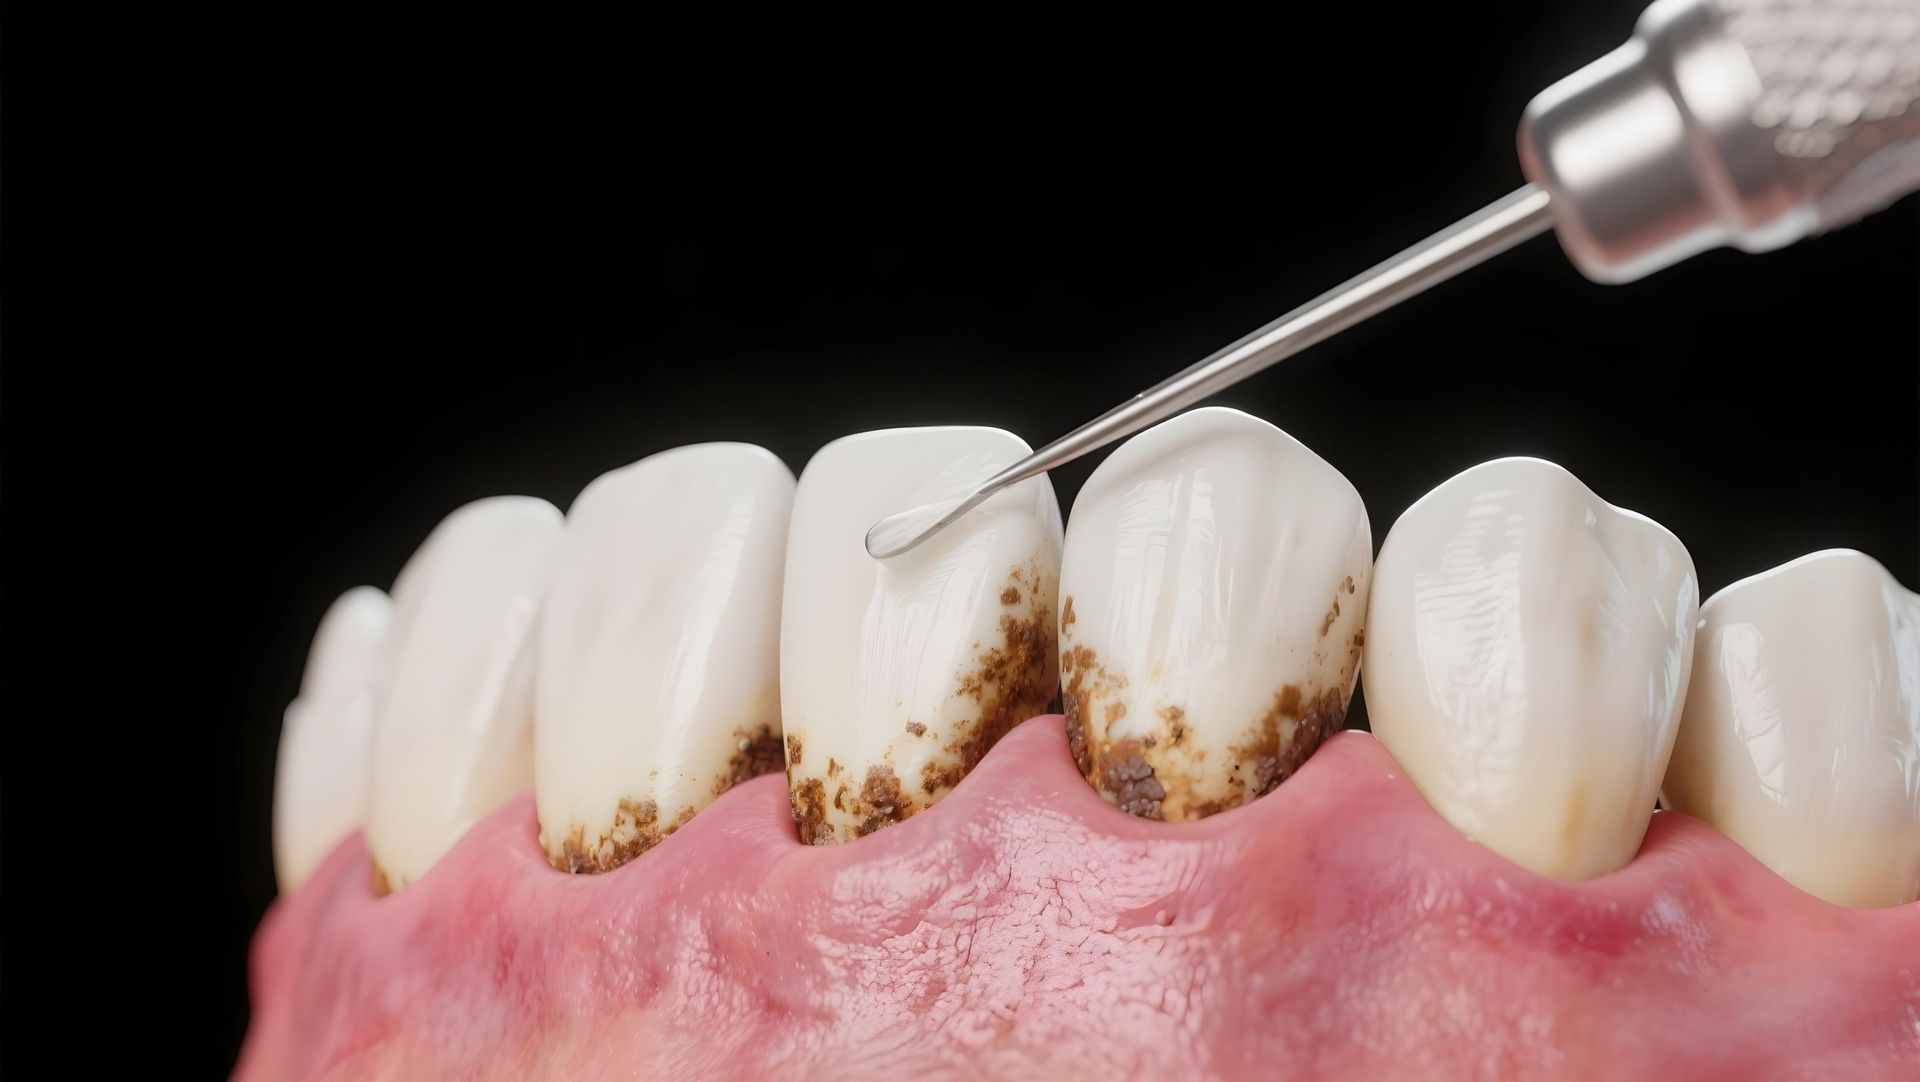

Igiene orale professionale

Trattamento eseguito dall’igienista per eliminare placca, tartaro e macchie. È fondamentale per prevenire carie, gengiviti e alitosi, mantenendo il sorriso sano e fresco.